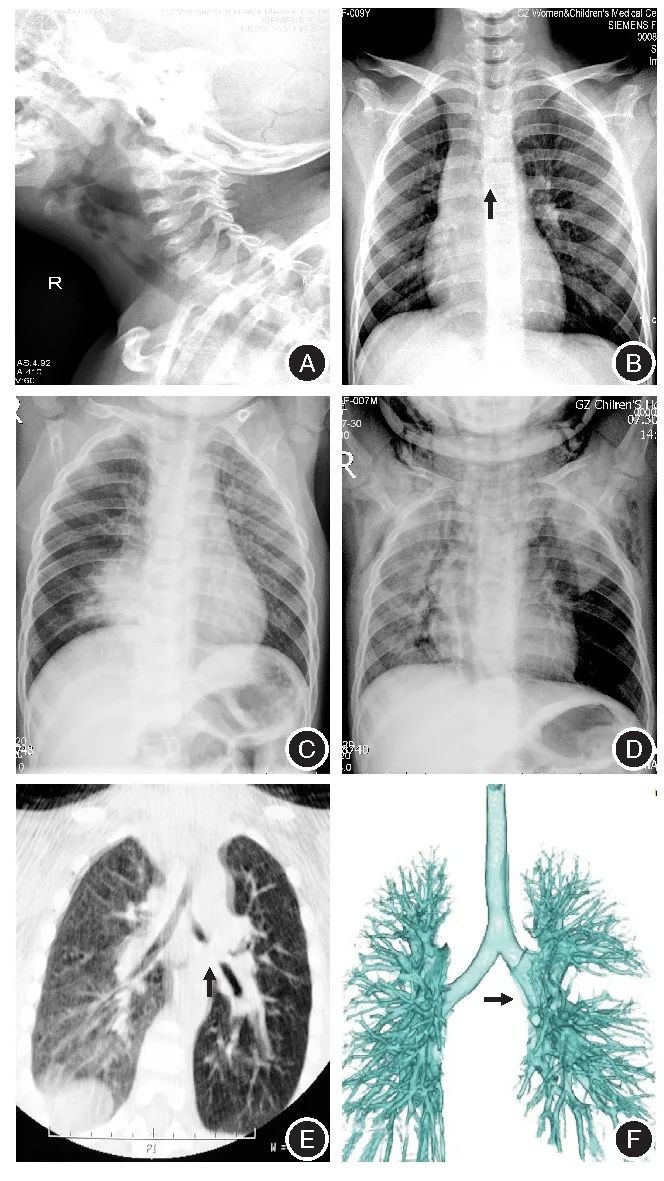

注:A,患儿男,2岁3个月,上气道异物——瓜子;B,患儿男,5岁,气管异物——硅胶管;C,患儿男,1岁10个月,支气管异物——花生,间接征象:右侧阻塞性肺气肿并肺炎;D,患儿男,2岁3个月,左支气管异物——瓜子,间接征象:肺气肿,纵隔气肿,皮下积气;E,患儿男,2岁,支气管异物——花生,左侧支气管内软组织密度影;F,患儿女,3岁,VR重建示左侧支气管气异物图1儿童呼吸道异物影像学特征